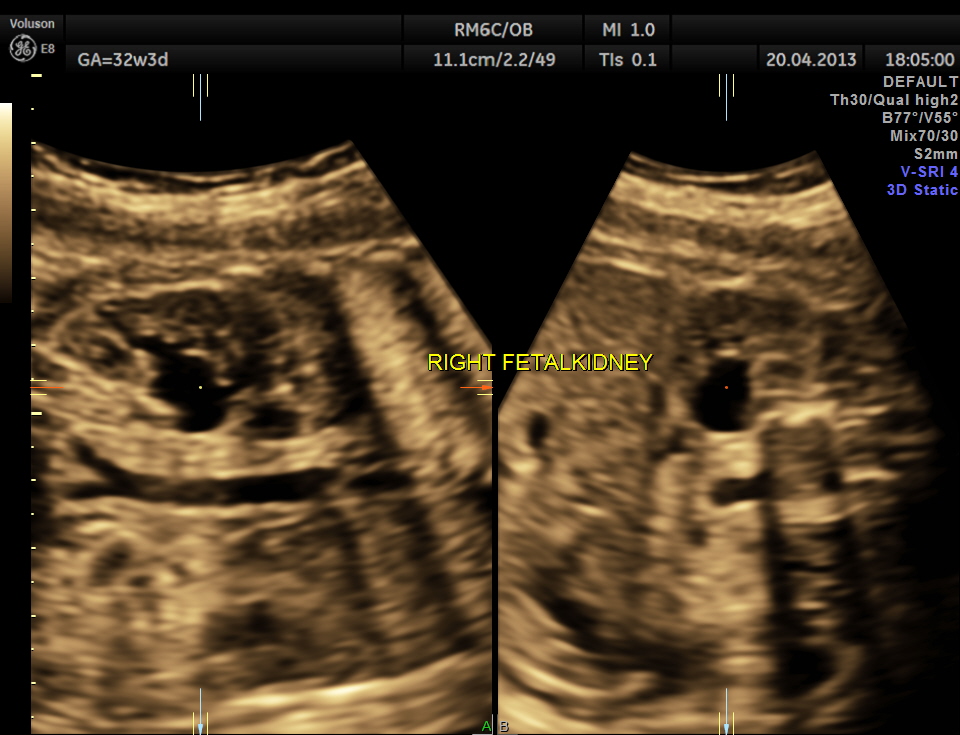

This was 26 year old lady, primigravida, without history of consanguinity.

Scan was done at 32 weeks of gestation. Earlier scans have been reported as normal.

The following images show bilateral renal pelvi ectasis and bilateral dilated ureters with all the changes more in the left kidney .

The left kidney also showed possible duple-ix pelvis with double ureters arising from them . But this finding could not be confirmed in all the views .

Axial images of kidney would better showed the urethral dilation